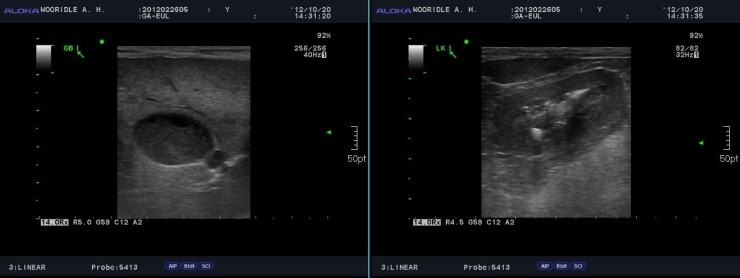

앞다리 골절 이력 발견하기: 강아지 앞다리 골절 수술 후 플레이트 문제입니다.쿠샤테리아/남아/중성화O/13세/2kg만성췌장염/담석증/2020년4월담석제거술/2021년5월담…blog.naver.com저는 “그 뒤 카미는 특히 증세는 보이지 않고 있다. 가끔 먹은 것을 토하다. 구토라기보다는 역류가 있는 듯했다. 사료를 삼키며 뒤돌아보면, 사료로 내뿜고 있었다.”정도를 말했다.카미를 바라보던 선생님은 키보드에 몇 글자 적어 카미를 데리고 진찰실로 올라갔다.그리고 카미가 진찰을 받은 50여분간의 떨리는 시간이 지나 카미와 함께 내려온 선생님께 다시 만날 수 있었다.선생님은 오늘 혈액 검사, 복부 초음파로 이상한 부분이 하나도 발견되지 않고 기존 확장된 담관은 5.5~6mm정도를 항상 유지하는 것처럼 보인다고 말씀하셨다.오늘의 담관도 5.5mm로 측정됐다고 한다. 그래서 이제는 검진 주기를 3개월이 아니라 6개월로 늘려도 좋겠다고 말씀하셨다.이전에도 “결과에 따라서 검진 주기를 내밀어 본다”라는 말은 몇번인가 들은 적은 있지만 실제로 그 날이 오다니. 처음에는 전혀 실감이 나지 않았다.선생님이 “그럼니는 이제 로우 패트가 아닌 다른 사료를 먹어도 괜찮습니까?”라고 묻자 선생님의 경험상, 담낭 수술을 받은 아이들이 사료를 교환하고(당장은 없어도)콜레스테롤이나 이상이 오는 것을 많이 봤으니 가능하면 사료는 교환하지 않는 것이 좋다고 말했다. 정교환하고 싶다면, 로우 팻이요와 일반 사료를 절반씩 섞어 먹여도 좋다고 말했다.선생님과의 대화를 마치고 6개월 후에 예약을 잡는데 다음의 내원 날이 9월이라니… 그렇긴. 갑자기 6개월간의 검사 주기가 실감되고 가슴이 벅찼다.이 가슴 뿌듯한 마음을 어떻게 표현할 수 있으랴.카미가 감탄해서 다시 감탄했다. 이렇게 작은 강아지가 나보다 더 잘 살아 있었다.부슬부슬 내리던 비도 달콤한 봄비가 됐다. 집으로 돌아오는데 우산을 열지 않고도 상큼했다.고마워 아가야고마워 아가야